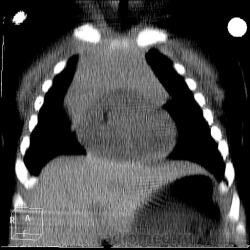

КТ грудной полости. Ребёнок 2 месяца.

Мама заметила, что сын начинает... свистеть при укладывании на живот. На обзорной рентгенограмме легких (к сожалению, не успела сфотографировать, ребёнка перевели в областную детскую больницу со снимком) рентгенолог описал образование верхнего и среднего средостения, слева в виде паруса. Интересно, что УЗИ сердца - норма, а про средостение узист ничего не написал...

Однако, тут без детских рентгенологов... тоскливо. Кроме расширения переднего средостения не знаю, что вижу. Впрочем, ещё трахея с бронхами и пищевод оттеснены кзади.

Картинок прибавилось. Это Тимус так увеличен?

Да, тимомегалия, вилочковая железа оттесняет кзади трахею и бифуркацию. Однородное образование с четким ровным контуром. Субплеврально врожденная парасептальная эмфизема.

Нет, только не тимома. Нормальный тимус для двух месяцев.

Ola-la виднее, не спорю. Я не педиатр, у меня только одна статья есть по вилочковой железе у детей, по ней и сужу. У малыша подсчитала объем тимуса по методике Воеводина - 47,25 см3 , при норме 18,4 - 43,5. На мой взгляд, правая доля немного увеличена, но не настаиваю.

Свист только лежа на животе (я думаю, что причина в тимусе). Не грубый звук. Ни срыгивания, ни кашля, ни цианоза. Про гортаноглотку ничего не скажу - не в курсе.

У детей немаловажное значение имеет непосредственное предлежание передней стенки трахеи к вилочковой железе, которая достигает максимального развития у 2-летнего ребенка, а затем медленно атрофируется. Резко гиперплазированная вилочковая железа оказывает давление на еще не сформировавшуюся и не окрепшую стенку трахеи с развитием тяжелого врожденного стеноза.